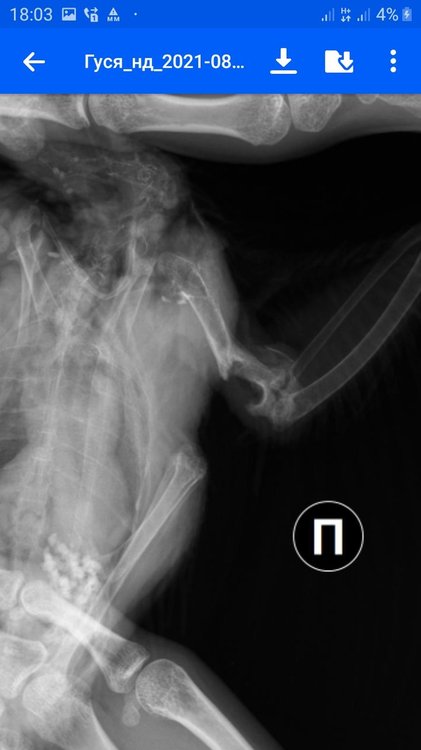

Скажите, какой должен быть рентген? В двух проекциях или какой???

Рнтген - для начала прямая ВД проекция. Как птицу раскладывать- есть на форуме. В позе Христа. Так быдет возможно визуализировать сустав.

Как у меня на прямой проекции в начале темы, как я поняла.

Произошла ужасная ситуация. Короче, в одной клинике отказали под непонятным предлогом. В другой сделали так .... что просто кость вылезла... и вся эта шишка, просто кусок кости отпал... я короче просто в шоке, там теперь просто открытая кость или я даде не знаю как сказать. Надо ставить уколы, чтобы там не пошла чернота. Я короче вообще просто в ауте.

Я не знаю, при снимке уже сместилась шишка или нет. Когда птицу перевернули, кость вылезла, чуть позже просто отпала...

Сустав отломился, рентген сделан незадолго до отлома